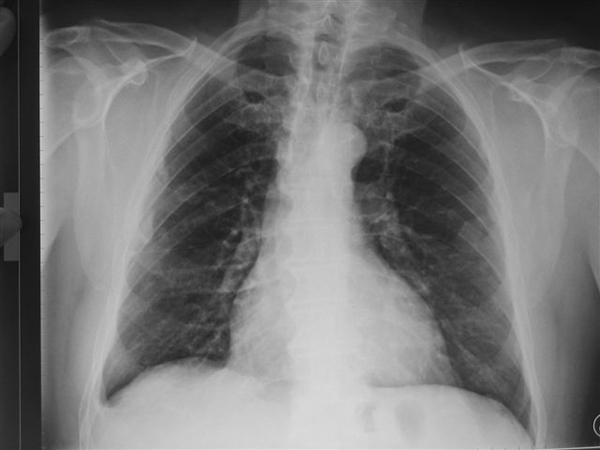

Radiographie des poumons montrant une pathologie liée à l’amiante